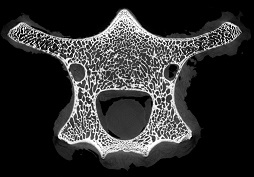

脊椎骨里的“笑臉表情包”

作者:ZZ 日期:2021-07-15 點擊數:14328次

micro CT不僅能夠獲得整體骨量的變化,還能獲得骨骼內部骨小梁骨微結構的定量指標,進而將骨小梁微結構指標、皮質骨指標及骨量結合起來,綜合評價骨強度和骨量在骨質疏松癥發生和發展中的作用。